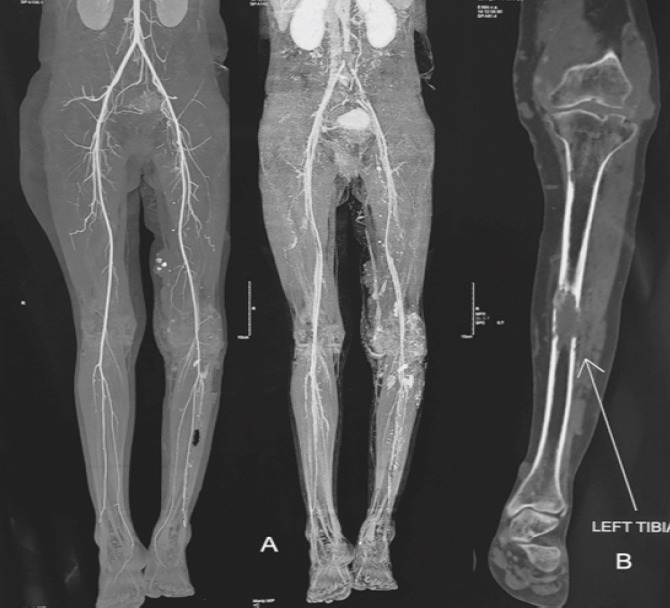

Case report: We present one such case of a young female who presented with chronic pain in the leg for 2 years and difficulty in walking. The clinical and radiological evaluation, including computed tomography angiography, confirmed the diagnosis of intraosseous venous malformation of the tibia. The lesion was managed initially by sclerotherapy and endovenous laser ablation by the intervention radiologist; however, the bony lesion required prophylactic intramedullary nailing in view of persistent pain affecting her daily activities.